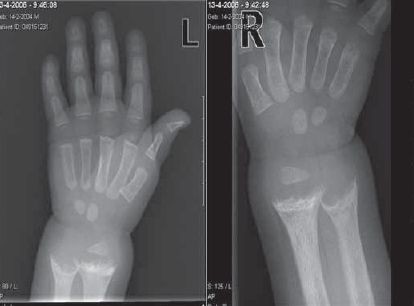

Youssef, zoon van Marokkaanse ouders, wordt op zijn 2e jaar naar de kinderarts doorverwezen omdat men op het consultatiebureau een hartgeruis heeft gehoord. Direct bij binnenkomst vallen zijn waggelende gang en zijn kleine gestalte op. Moeder vertelt dat Youssef een goede conditie heeft en weinig ziek is. Op het consultatiebureau was de kleine lengte wel opgevallen, maar dit was nog geen reden tot nader onderzoek. Moeder vertelt dat Omar Youssef maanden borstvoeding heeft gehad. Hierbij gaf zij hem af en toe vitamine-D-druppeltjes. Youssef kwam regelmatig buiten. Bij lichamelijk onderzoek werd een kleine jongen gezien met een lengte van 81,7 cm (–2,5SD) en een gewicht van 12,5 kg (+1SD). Men zag een duidelijke verdikking van beide polsen, knieën en enkels. Verder waren beide benen sterk gebogen, rechts meer dan links (figuur 1). Bij auscultatie van het hart was er een functionele souffle hoorbaar. Rachitis uit zich bij peuters vooral in gebogen benen.3 Bij Youssef dacht men dus aan dit ziektebeeld. Daarom werd aanvullend laboratoriumonderzoek gedaan en een polsfoto gemaakt. Laboratoriumonderzoek leverde het volgende op: normaal serumcalcium (2,40 mmol/l), verlaagd fosfaat (0,83 mmol/l, N > 1,15), verhoogd alkalische fosfatase (1100 U/l, N < 120), verlaagd 25.(OH)D2 (3 (24 nmol/l, N > 50). De röntgenfoto van de pols toonde een pathognomonisch beeld voor rachitis met distale indeuking (cupping) van de ulna en de radius (figuur 2). Bovendien bleek het totaal 25-hydroxyvitamine D van de moeder verlaagd (25 nmol/l, N > 50). Het feit dat met name het 25.(OH)D2 sterk verlaagd was, duidt op een voedingsgerelateerde oorzaak van de rachitis. Voor de hand ligt een relatie met de langdurige borstvoeding, waarbij onvoldoende vitamine-D-suppletie gegeven werd. Als behandeling werd dan ook gestart met vitamine D.